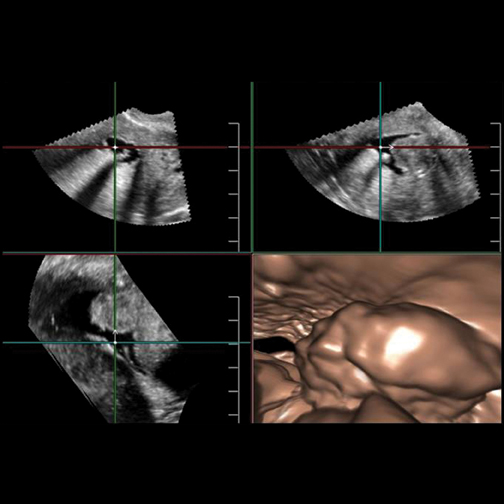

Additionally, limitations with 2-D ultrasound for interventional applications have many clinicians looking toward 3-D and 4-D ultrasound for real-time volume imaging, made possible by the continuous increase of computing power in ultrasound systems. RSNA 2012 marked the one-year anniversary of Toshiba’s launch of the Aplio 300 and 500 systems, the latter of which offers 3-D and 4-D applications for clinical use. The Aplio 500’s Fly Thru technology allows operators to “fly through” and explore fluid-filled interior ducts and vessels during or after the examination. Its Smart Fusion technology provides the ability to synchronize ultrasound imaging with computed tomography (CT) or magnetic resonance (MR) image, improving the detection of hard-to-find lesions.

In combination with advanced visualization functions, 3-D ultrasound can aid complex surgical applications and interventional procedures, according to Leen. Images are reconstructed from echoes sent by the transducer from multiple angles, and with 4-D ultrasound real-time moving images can be produced. Multiplanar reconstructed (MPR) images are now available for review in the same manner as CT and MR scans, Leen said.